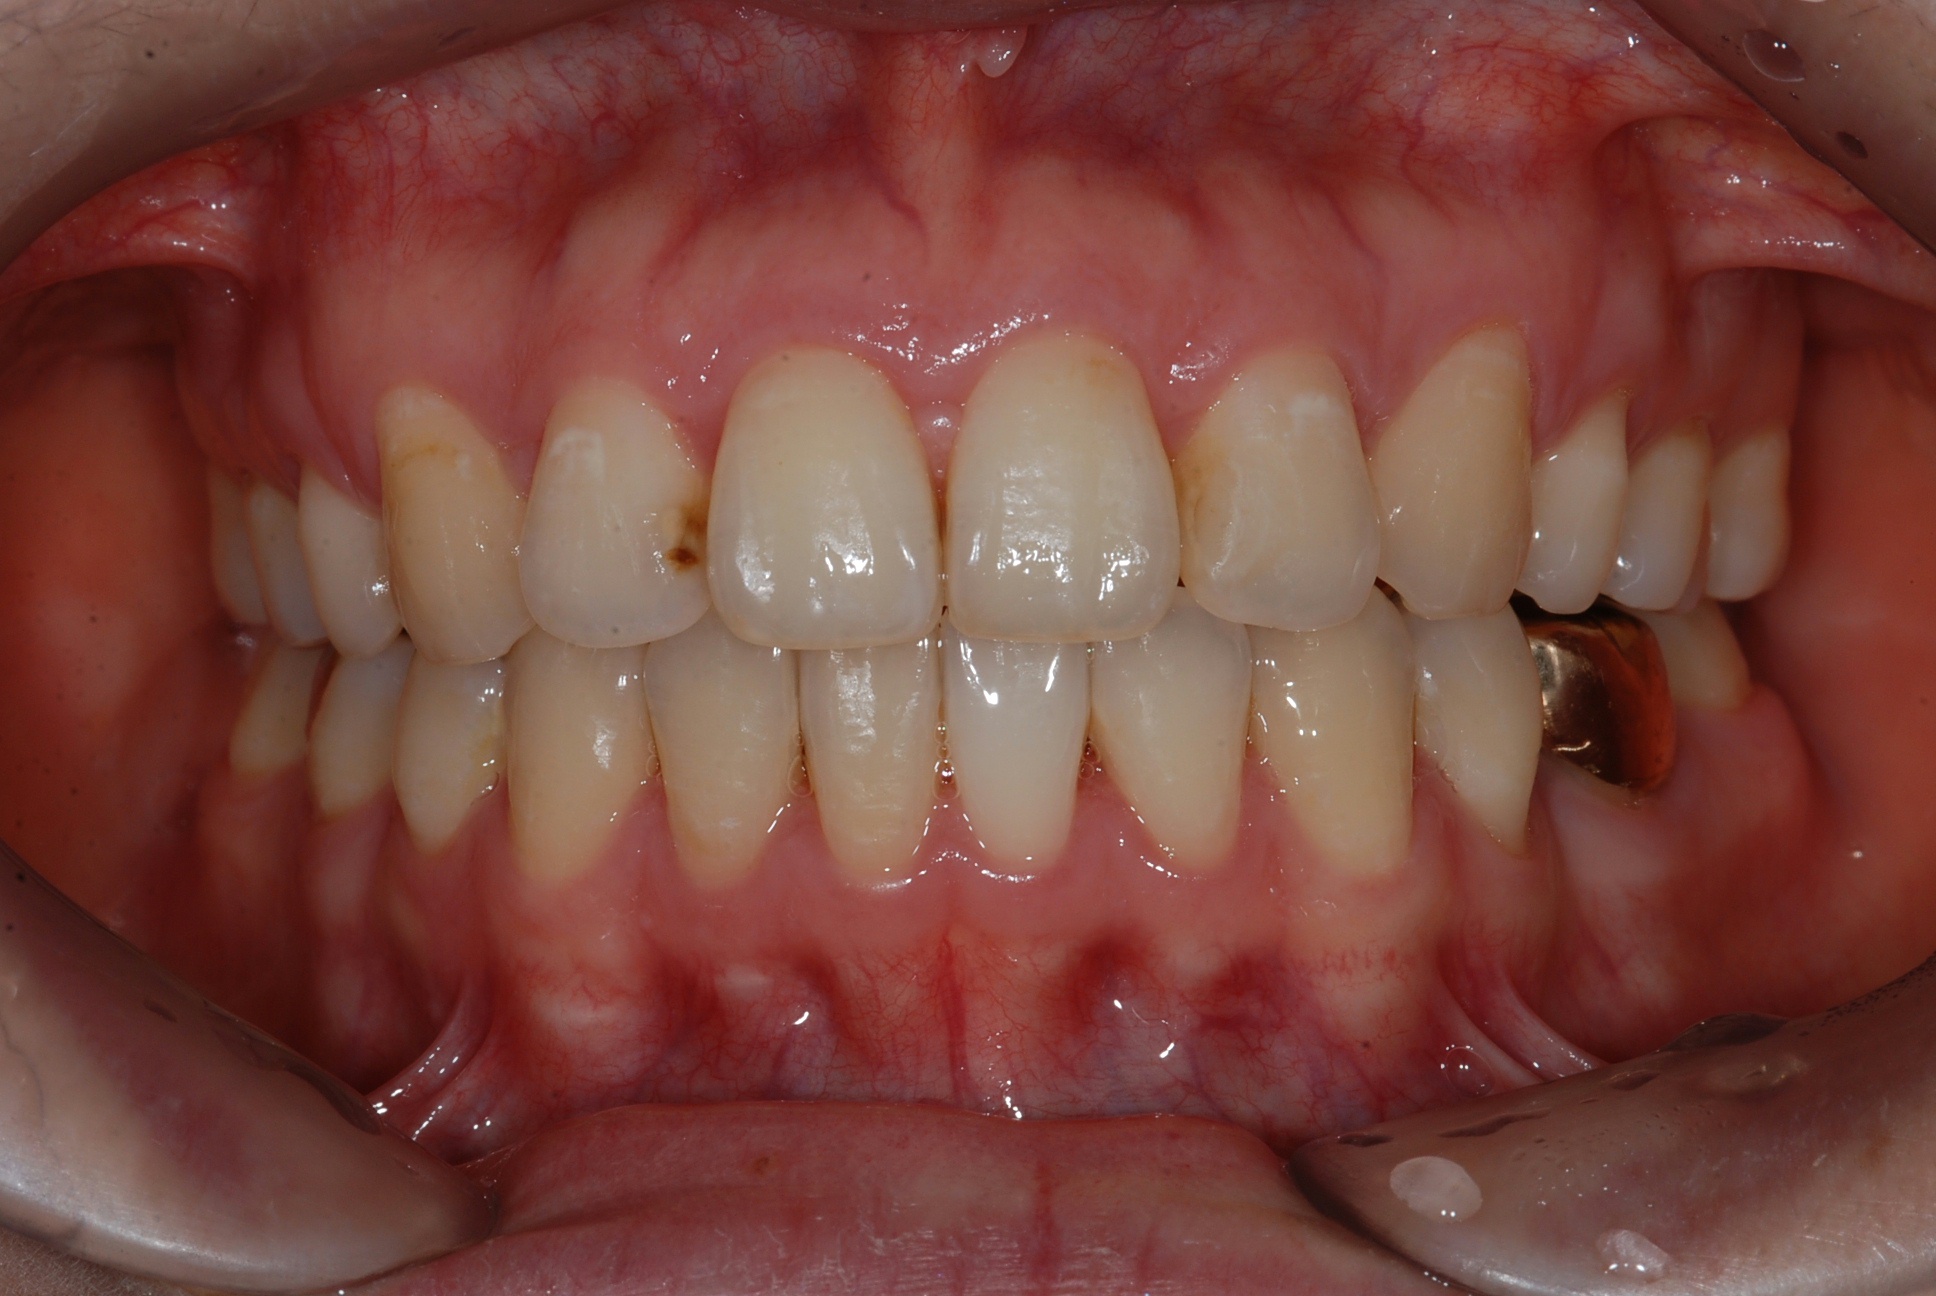

치료 후 사진입니다.